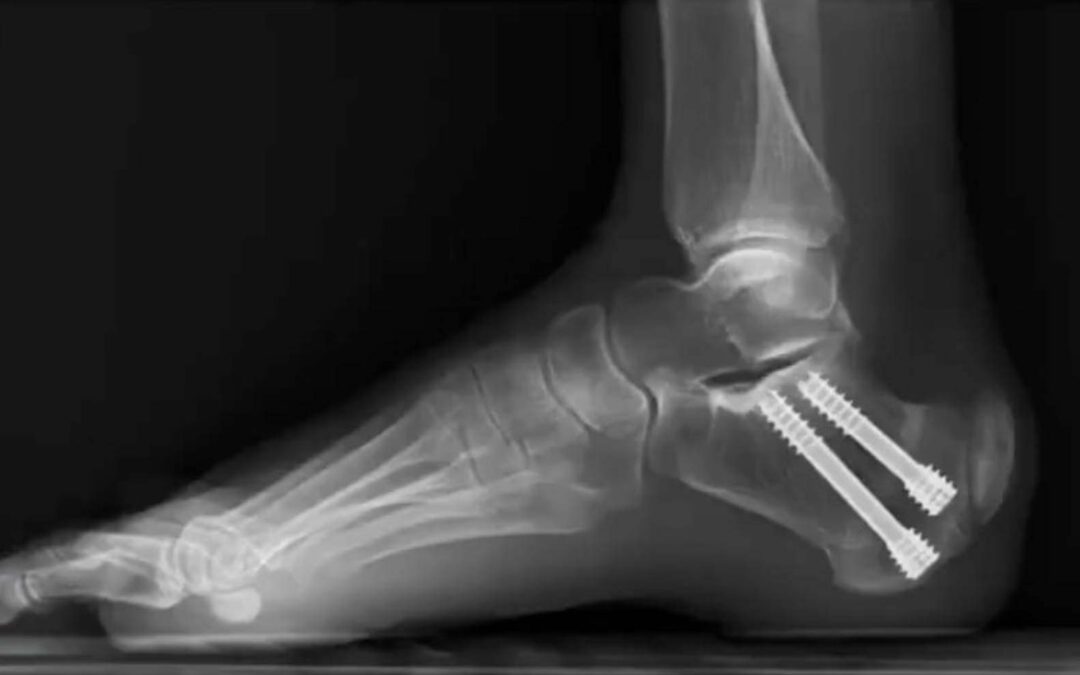

The core premise of the Zadek procedure is to change the biomechanical environment to allow the body to heal itself. By making a small cut in the heel bone and removing a wedge, the surgeon alters the angle by which the Achilles tendon inserts on the calcaneus. This decompresses the entire area, alleviating the tension and strain that caused the inflammation and pain in the first place, while allowing the tendon to heal naturally.

The technical key to the Zadek osteotomy is a dorsal closing wedge osteotomy to change its angle and decompress the Achilles tendon. But how big should that wedge be? It turns out that size is critical.

During their discussion, Dr. Jeff Dykis offered a perfect analogy for this concept: “Goldilocks and the 3 bears.” This has led researchers to ask what the sweet spot for the wedge size is perhaps not too big, or not too small–but “just right.” It is now generally accepted that a wedge usually 10 mm is to be removed from the calcaneus to allow patients the maximal biomechanical advantage postoperatively, however not smaller than this. Based on current data and extensive clinical experience, the guesstimated sweet spot is somewhere between 10 mm and 12 mm. If < 10 mm is removed, there is likely not enough wedge removed from the calcaneus to allow for adequate decompression on the Achilles which may result in a poor outcomes.